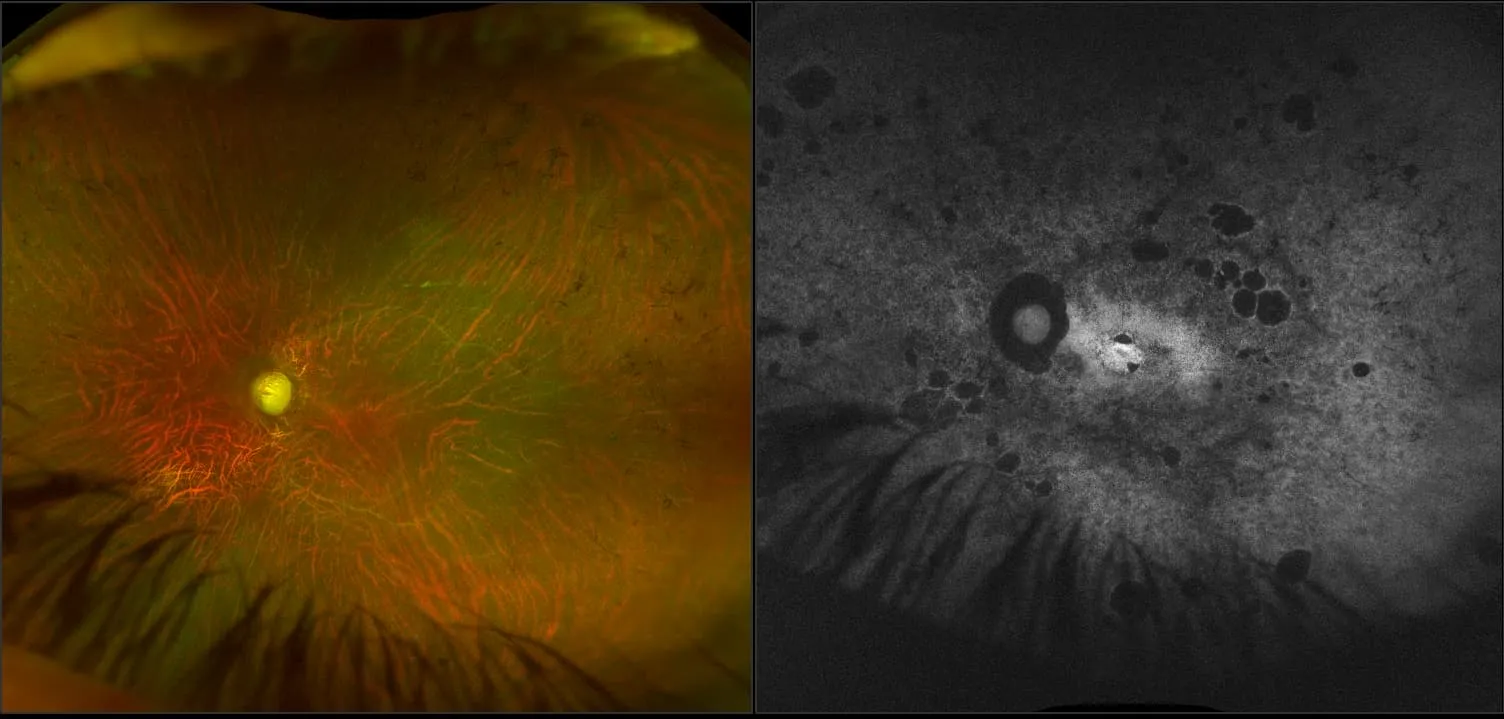

optomap® Recognizing Pathology

This material is designed as a searchable reference resource to support clinical decision-making. The information contained here should be used as general guidance when viewing optomap and OCT images from Optos devices. The differential diagnosis should be made under the direction of the responsible physician. These images were taken on the latest ultra-widefield optomap devices.

The Cases and Images

optomap Recognizing Pathology is searchable by pathology and/or optomap image modality. You may search by multiples of each selection. Each individual case is represented by the accompanying thumbnail image. Most cases include several different optomap image modalities. To view a full description of the case, please click on the thumbnail. Each image in the case will be made available through our OptosAdvance software which provides multi-dimensional visualization of digital images to aid in the analysis of anatomy and pathology. Support and pathology definitions can be found by selecting one of the buttons, above. Should you have questions, please complete the form below.